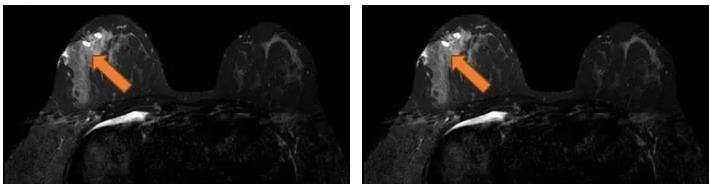

2021.7.6 钼靶示:右乳外上象限肿块,考虑乳腺癌(BI-RADS-5类)右腋下肿大淋巴结,M灶可能。

右乳外上象限不规则高密度肿块,边缘毛糙,大小约3.3×2.7cm,邻近皮肤牵拉增厚,右腋下见肿大淋巴结。

图2. 钼靶

(3 cycle 后)2021.9.21 钼靶示:右乳外上象限不规则形肿块明显缩小,右腋窝淋巴结亦较前缩小。

图6. 钼靶